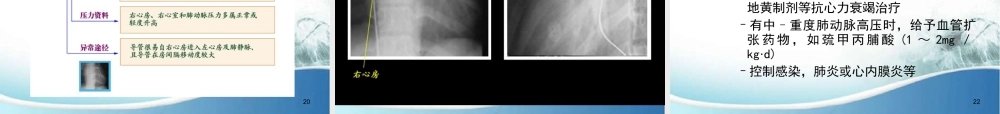

小儿心血管系统疾病张晓丹安徽省第二人民医院儿科2(二)房间隔缺损房间隔缺损(ASD)是常见的先心病之一,其发生率约占先心病的20-30%,其中继发孔ASD多见,原发孔ASD、静脉窦ASD和冠状静脉窦ASD少见。继发孔ASD自然闭合多在4岁之内,闭合率为15%,其他型ASD不能自闭。房间隔的形成胚胎第4周开始病理解剖继发孔缺损•为第一房间隔吸收过多或第二房间隔发育障碍所致,此型临床多见。原发孔缺损•多由第一房间隔过早停止生长所致.此类较少见。若伴有二尖瓣前叶裂缺又称之为不完全性房室通道。456•RA血流量增加,RV扩大、肥大•肺循环充血(多血)•体循环供血不足(少血)7临床表现主要取决于缺损及其分流量的大小•症状–缺损小,分流量少者可无任何症状–缺损大,分流量多时(肺体循环量比>1.5:1)体循环不足的表现:面色苍白,瘦长,乏力肺循环充血的表现:可有活动后心悸、气短、暂时性青紫,易发生呼吸道感染–婴幼儿多数少症状,常在体查时被发现8临床表现•体征–一般情况多数发育正常,无发绀–心脏检查特点不同程度的右心扩大一般无震颤胸骨左缘第2~3肋间听到Ⅱ~Ⅲ/Ⅵ级收缩期喷射性杂音P2增强,S2固定分裂9X线检查•缺损小者可无改变•分流量大者主要显示–双肺血管影增多,呈肺多血改变–肺动脉段突出,可见肺门“舞蹈征”–右心房、右心室扩大–主动脉结较小–心胸比例扩大10心电图心电图对诊断ASD具有重要价值12超声心动图•M-modeEchocardiogram:98%显示右心房、右心室腔扩大,室间隔与左心室后壁呈同向运动•2DEchocardiogram:剑下和胸骨旁四腔位可直接显示房间隔连续中断,断端呈火柴棒样•ColorDopplerFlowImage:可见到伪彩色血流自左心房经ASD流向右心房13141516171819心导管检查2021ASD的治疗•内科治疗主要针对并发症治疗,监测肺动脉压力,指导喂养,保障发育–有心力衰竭者应限制活动,常规应用洋地黄制剂等抗心力衰竭治疗–有中–重度肺动脉高压时,给予血管扩张药物,如巯甲丙脯酸(1~2mg/kg·d)–控制感染,肺炎或心内膜炎等22ASD的治疗•介入性心导管疗法—经导管ASD封闭术–医学领域的一项重大技术革新–1976年始–1997年始用Amplatzer双盘形封堵器封堵ASD23ASD的治疗适应症:年龄:通常≥2岁直径为4-36mm的继发孔中央型ASD,存在左向右分流缺损边缘至冠状静脉窦,上、下腔静脉及肺静脉的距离≥5mm;房室瓣≥7mm房间隔伸展径≥ASD直径+14mm不合并需外科手术的其他心脏畸形2425AmplatzerOccluderAmplatzerOc...